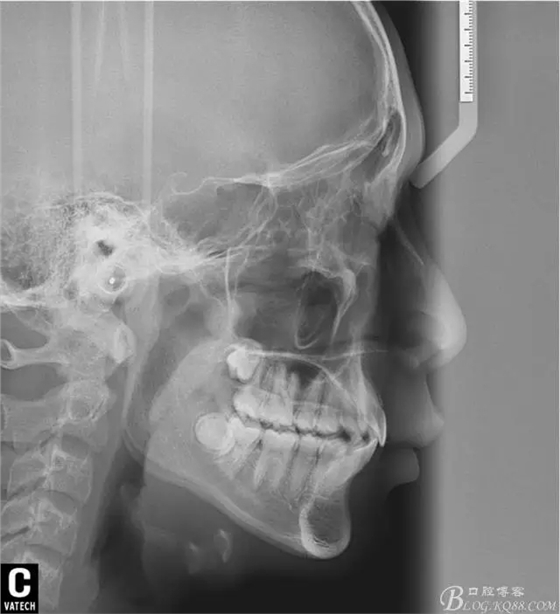

術(shù)后全景,側(cè)位照。